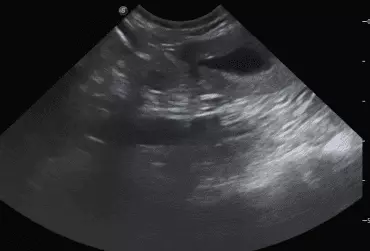

Badanie USG suki rasy Whippet w 28 dniu ciąży